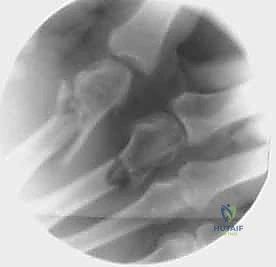

- الأشعة السينية (X-rays): يتم أخذ صور من زوايا متعددة (أمامية خلفية، جانبية، ومائلة) لتحديد موقع الكسر، نوعه (عرضي، حلزوني، مائل، متفتت)، ودرجة التزوي (Angulation).

خطوات التثبيت الجراحي - توثيق بصري (Intraoperative Imaging)

يحرص الدكتور هطيف على توثيق خطوات العمل الجراحي لضمان أعلى مستويات الدقة. نستعرض هنا مجموعة من الصور من داخل غرفة العمليات توضح مدى تعقيد ودقة هذه الجراحات:

معرض الصور الشعاعية: تقييم النتائج الجراحية (Post-Op X-rays)

النجاح الحقيقي يُقاس بالاستعادة المثالية للشكل التشريحي للعظم. توضح هذه الصور الشعاعية بعد الجراحة الدقة المتناهية في إعادة محاذاة العظام وتثبيتها.

التثبيت المحكم يسمح بالشفاء العظمي الأولي (Primary Bone Healing) دون تكوين كتلة عظمية كبيرة (Callus) قد تعيق حركة الأوتار المنزلقة فوقها.